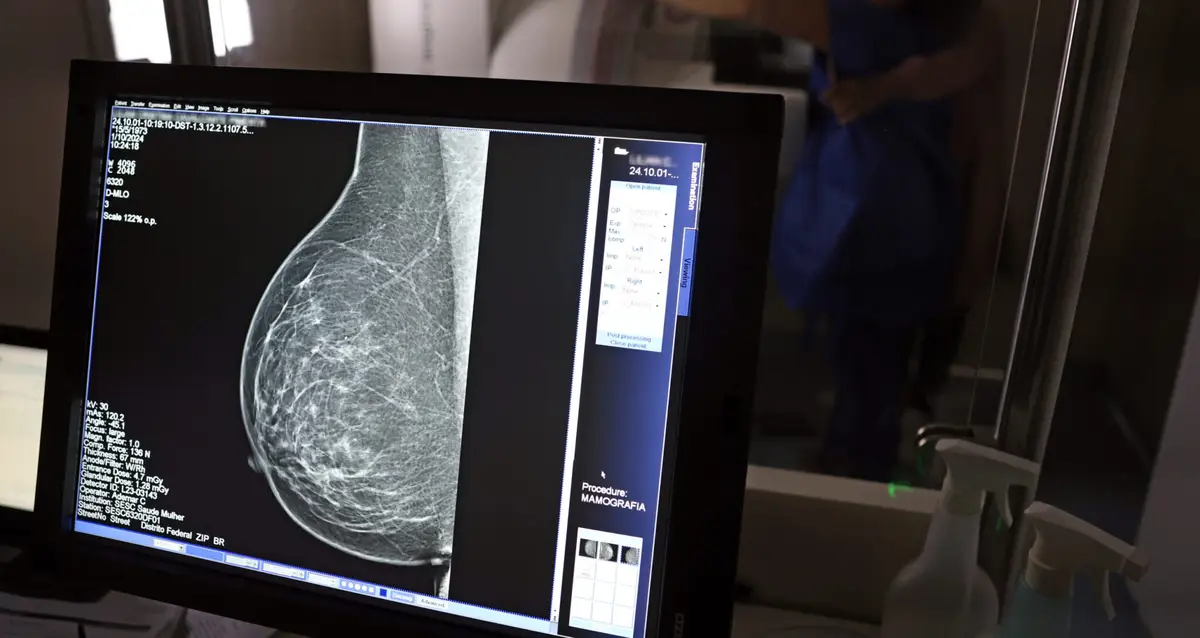

Estado amplia diagnóstico precoce e reforça tratamento contra doençaCom mais de 57 mil mamografias realizadas em 2025, o Piauí ampliou significativamente o acesso ao diagnóstico precoce do câncer de mama, especialmente entre mulheres a partir dos 40 anos. Como parte das ações de reforço ao tratamento, o estado recebeu, na quinta-feira (23), uma remessa com 224 unidades do medicamento Trastuzumabe Entansina, recém-incorporado ao Sistema Único de Saúde (SUS) para casos avançados da doença.

A rede estadual conta com 43 mamógrafos fixos e o serviço itinerante dos Caminhões da Mamografia, que percorrem os municípios levando o exame a quem mais precisa. O foco principal tem sido nas mulheres entre 40 e 49 anos, faixa etária que passou a ser atendida sob demanda, conforme nova orientação do Ministério da Saúde.

A técnica em radiologia Ana Vitória atua na Central de Diagnóstico de Valença e confirma o impacto direto na vida da população. “Antes o exame só era disponibilizado em clínica particular. Agora, mulheres de toda a região vêm aqui, fazem o agendamento e realizam o exame. Atendemos mulheres a partir dos 40 anos, sem fila, com estrutura pública. Isso melhorou muito a vida das pessoas”, afirma.